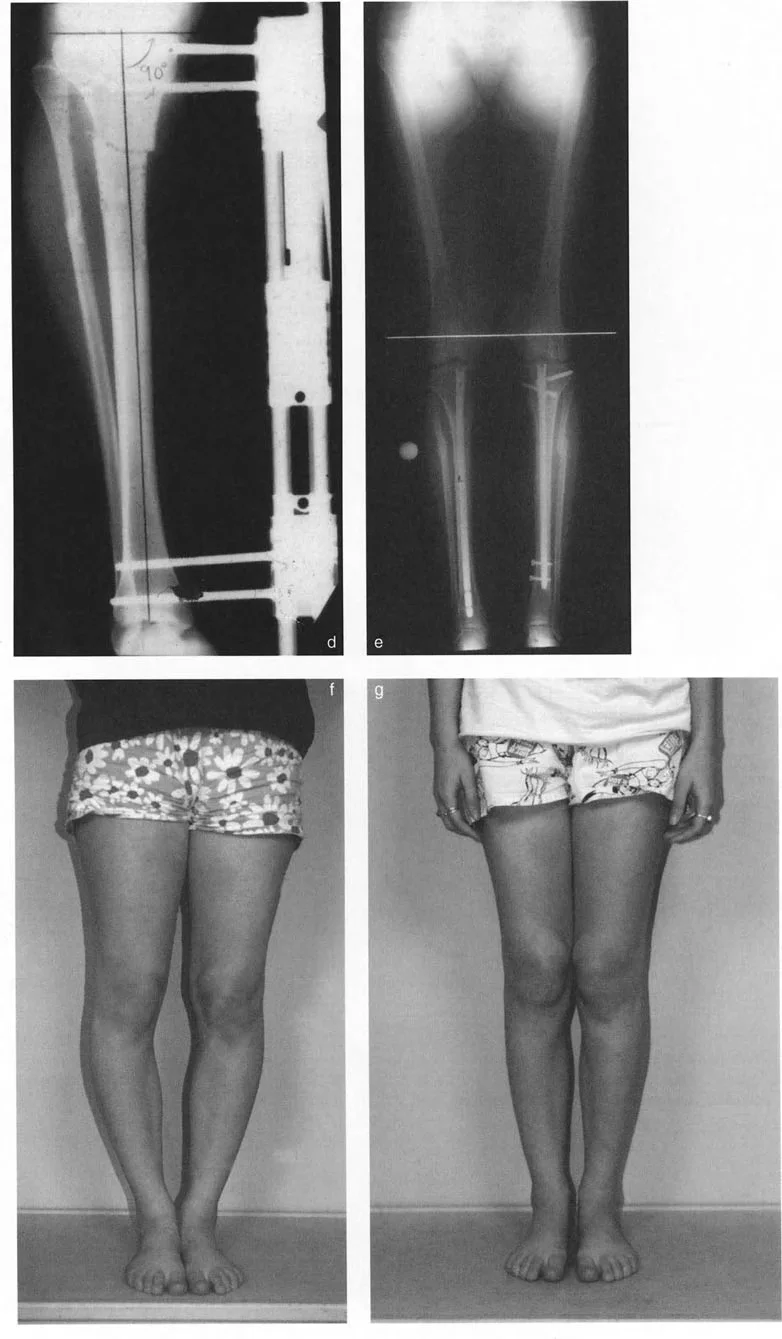

Mechanical Axis Deviation MAD

Mechanical Axis Deviation (MAD) is the perpendicular distance from the mechanical axis of the entire lower limb to the center of the knee joint. It is the definitive test for global limb malalignment.

- Normal MAD: The mechanical axis normally passes slightly medial to the exact center of the knee joint. The normal MAD is approximately 8 mm (± 7 mm) medial to the center of the knee.

- Pathologic MAD: A mechanical axis passing excessively medial to the knee center indicates a varus alignment. This predisposes the patient to medial compartment osteoarthritis due to pathologic compressive forces. Conversely, a mechanical axis passing lateral to the knee center indicates a valgus alignment, predisposing the patient to lateral compartment osteoarthritis.

Step 1 The Malalignment Test

Begin with a 51-inch standing AP radiograph. Draw the mechanical axis of the entire lower limb (center of femoral head to center of ankle). Measure the Mechanical Axis Deviation (MAD).

* If the MAD is normal (8 mm medial to knee center), global alignment is normal.

* If the MAD is abnormal, proceed to Step 2.